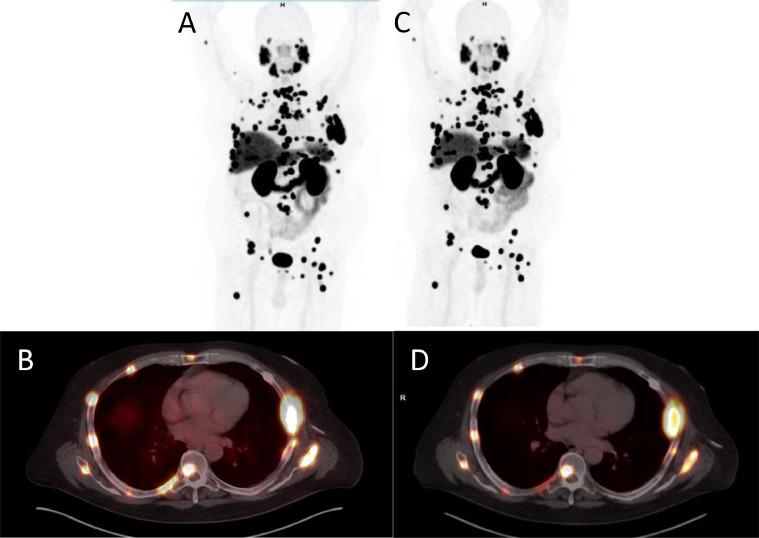

The clinical utility of gallium 68 (Ga)-PSMA PET for the diagnosis and management of prostate cancer is driven in part by radioisotope availability and production costs. This study evaluates the equivalence between the two manufacturing processes for Ga-PSMA: Ga-PSMA-cyclotron (from a solid target) and Ga-PSMA-generator. A prospective, single-arm, single-institution non-randomized study was conducted where 16 patients with prostate adenocarcinoma underwent PET/CTs consecutively within 12 to 48 hours with each type of manufactured Ga-PSMA between December 2020 and June 2021. The intraclass correlation coefficients suggested acceptable reliability in all lesion parameters (ICC > 0.70). Bland-Altman analysis demonstrated acceptable bias levels for all lesion parameters. Thereby Ga-cyclotron (solid target) and Ga-generator production methods tagged to the same PSMA ligand resulted in scans which were deemed to be equivalent in detecting PSMA+ lesions in our study. As cyclotron-produced, solid- target Ga can be made in large (Ci) quantities, it is a promising tool for future application in Ga-PSMA PET scans with the potential to decrease radiotracer production costs and increase isotope availability.

镓68(Ga)-前列腺特异性膜抗原(PSMA)正电子发射断层扫描(PET)在前列腺癌诊断和管理中的临床应用部分受到放射性同位素可用性和生产成本的驱动。本研究评估了Ga-PSMA两种制造工艺之间的等效性:回旋加速器生产的Ga-PSMA(来自固体靶)和Ga-PSMA发生器。开展了一项前瞻性、单臂、单机构非随机研究,2020年12月至2021年6月期间,16例前列腺腺癌患者在12至48小时内先后接受了两种类型制造的Ga-PSMA的PET/CT检查。组内相关系数表明所有病变参数的可靠性均可接受(ICC>0.70)。布兰德-奥特曼分析显示所有病变参数的偏差水平均可接受。因此,在我们的研究中,标记有相同PSMA配体的回旋加速器(固体靶)生产的Ga和发生器生产方法所得到的扫描结果在检测PSMA阳性病变方面被认为是等效的。由于回旋加速器生产的固体靶Ga能够大量制备(居里),它是未来应用于Ga-PSMA PET扫描的一种有前景的工具,具有降低放射性示踪剂生产成本和提高同位素可用性的潜力。